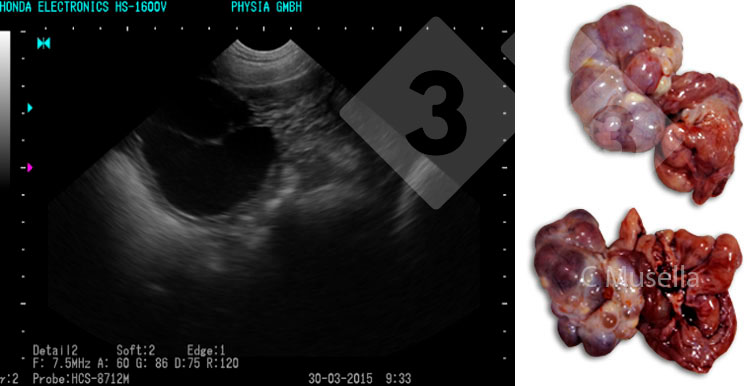

O diagnóstico de cistos ovarianos únicos ou múltiplos é relativamente simples, embora a identificação completa do tipo de cisto por ultrassom nem sempre seja certa.

Em relação às estruturas uterinas, a presença de fluido, não atribuível à gestação, sêmen ou calor, deve ser considerada patológica e indicativa de uma inflamação exsudativa no útero. A observação ultrassonográfica do exsudato só é possível em casos de inflamação aguda.